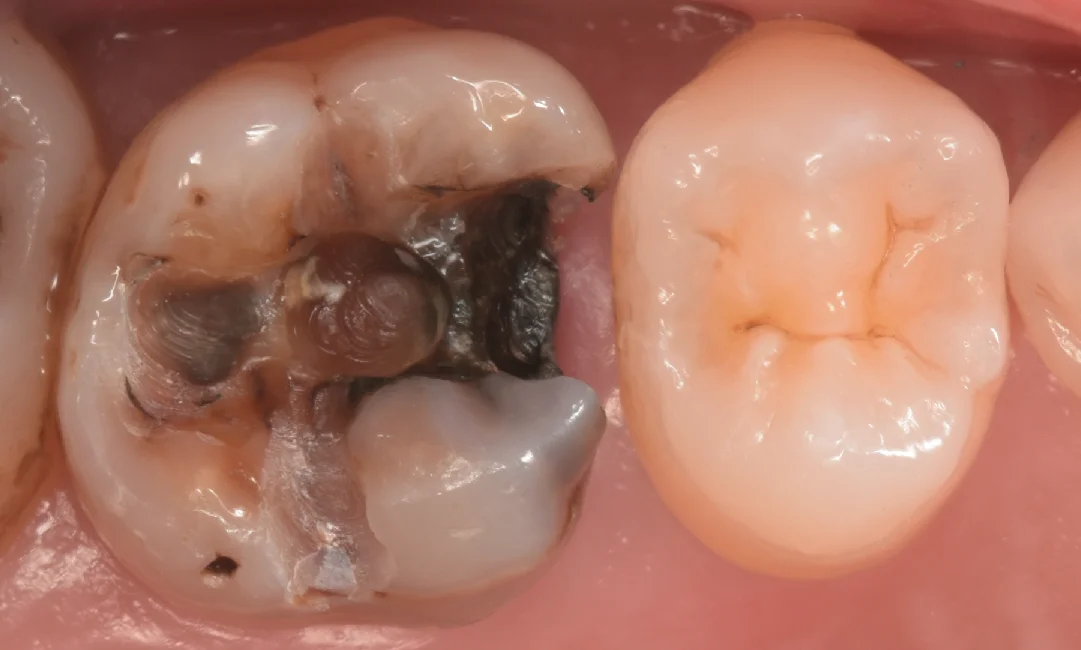

まずは術前からです。

今回は画面左側の金属部分と古い詰め物を除去してダイレクトボンディングを行なって行きます。

こちらの歯もこの先生が幼い頃に近隣の歯科医院にて治療を受けたようですね。

この金属は平成になったあたりで国内では使われなくなったと言われているアマルガムという材料になります。

通常歯科で使用する材料は硬化する際に収縮するのですが、アマルガムについては膨張するため、歯と材料の間に隙間ができづらく非常に優秀と言われたいたのですが・・・

この材料は歯と接着されているわけではないので、残っている歯に亀裂が入ったり、欠けたアマルガムから虫歯になるため実は結構予後が悪いです。

非常に小さなアマルガムであればあるいは・・・と言ったところですが、今回のように歯と隣の歯の方まで覆われている場合は非常に持たないイメージです。

今回は歯科医師という職も相まって非常に長い経過を辿りましたが・・・残念ながら限界のようですね。。。

また、アマルガムと接するようにコンポジットレジンが詰められているのですが、コンポジットレジンは金属とまともに接着できないため、その隙間から内部に細菌が侵入していると考えられます。

金属と古い詰め物を除去して虫歯を見やすくしたのがこちらになります。

全体的に黒くなっているのがわかるかと思います。

また、隣の歯との間については歯茎の下まで黒くなっているのがわかります。